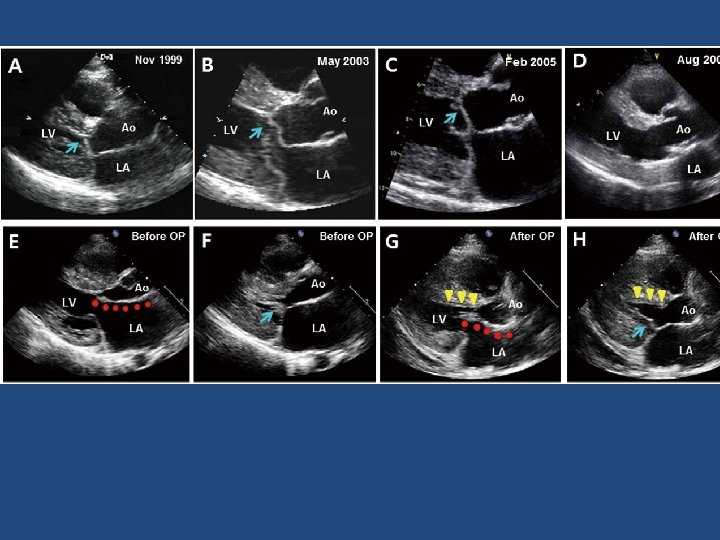

Elongated mitral leaflet causing SAM Christine Rodger British Heart Journal, 1976, 38, 732 -737.

Summary Michael Ibrahim et al. Eur J Cardiothorac Surg 2012; ejcts. ezr 232 © The Author 2012. Published by Oxford University Press on behalf of the European Association for Cardio-Thoracic Surgery. All rights reserved